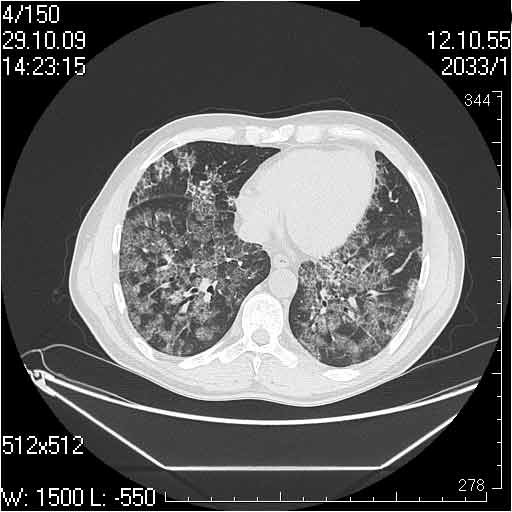

Случай №2

Мужчина 54 лет

Случай 2: картина патологических изменения довольно типична: GGOs & thickened interlobular septas = "crazy paving" sign. Наличие плотностей по типу матового стекла в сочетании с утолщением междолевых перегородок, даёт признак булыжной мостовой; на первом месте будет стоят диагноз альвеолярных протеиноз.